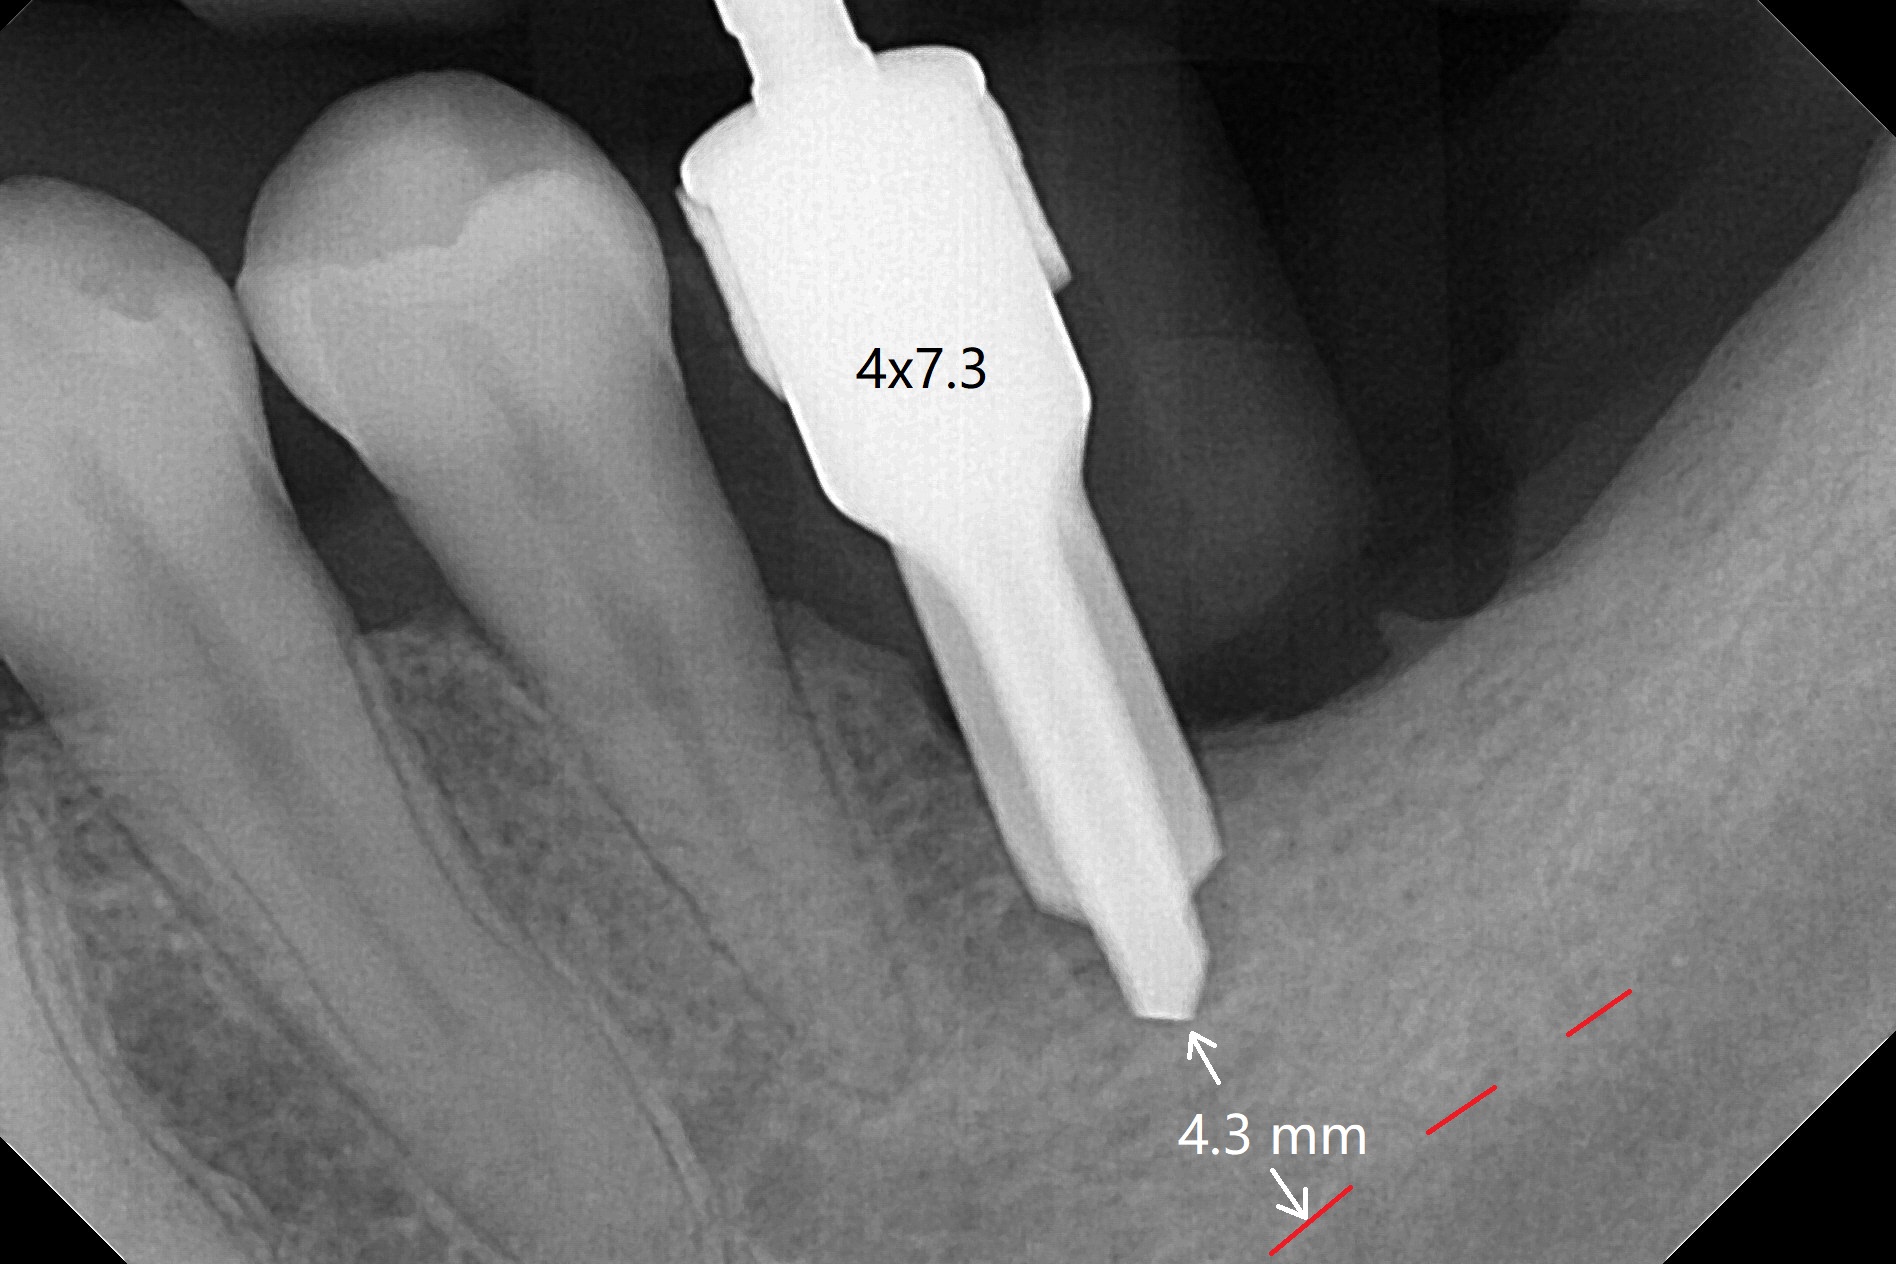

After use of 4x7.3 mm drill with guide, the buccal osteotomy height is 4 mm at #19, unsuitable for 4x5 mm Bicon implant, which requires 3 mm subcrestal placement. PA shows 4.3 mm bone from the Inferior Alveolar Canal (IAC, red dashed line (the superior border)). Following 4x8.5 mm drill, a 4x7 mm IBS implant is placed with distobuccal thread exposure and 3.2 mm clearance from IAC. With 3.5x10 mm drill less full length, the implant is placed a little deeper (10 Ncm). Bleeding spots created (Fig.3), sticky bone (cortical, fine granule) is placed (Fig.4 *), which is covered with PRF membrane and Colla tape. 4-0 PGA is used. There is no postop paresthesia. The length discrepancy is probably due to distal free end guide, which produces mesial placement of the implant. Try to make a premolar-sized crown. Use profile drill in uncover.